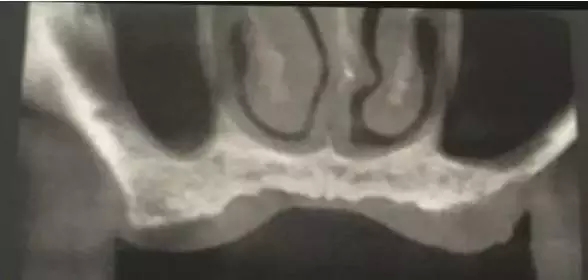

患者50歲,男性,身體健康。左上6,7缺失,骨高度2mm。

術(shù)前口內(nèi)照和CT片。